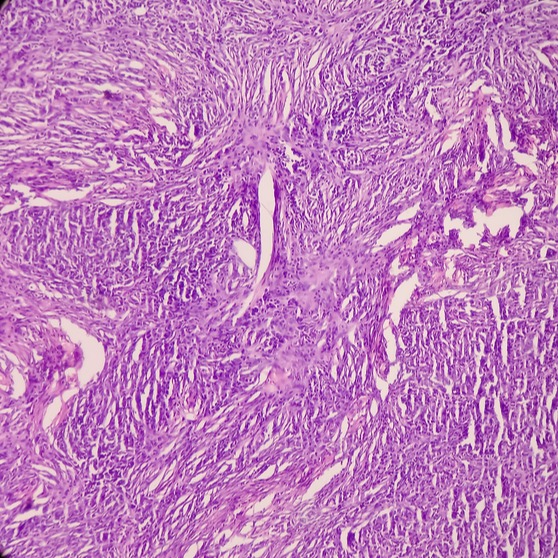

La diagnosi di dermatofibroma viene posta da uno specialista dermatologo e si basa dapprima su un esame obiettivo, che consiste nell’osservazione e nella palpazione del nodulo. In genere, questa procedura può essere sufficiente per dare una diagnosi definitiva.Tuttavia, poiché i sintomi dei dermatofibromi possono sovrapporsi a quelli di altre condizioni cutanee, come lipomi, neurofibromi o altre lesioni cutanee, il dermatologo potrebbe richiedere un esame più approfondito. In questi casi l’esame di riferimento è rappresentato da una biopsia cutanea, che consiste nella rimozione di un piccolo campione di tessuto dal dermatofibroma, che viene quindi analizzato in laboratorio attraverso un esame istologico. La procedura consente di accertare la natura benigna della lesione ed escludere eventuali tumori della pelle maligni.